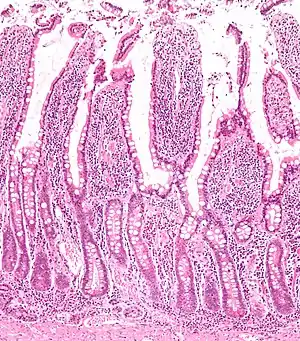

The three sections of the small intestine look similar to each other at a microscopic level, but there are some important differences. The parts of the intestine are as follows:

| Mucosa: intestinal epithelium | Simple columnar. Contains goblet cells, Paneth cells | Similar to duodenum, but the intestinal villus is long | Similar to duodenum, but the intestinal villus is short |

Digested food is now able to pass into the blood vessels in the wall of the intestine through either diffusion or active transport. The small intestine is the site where most of the nutrients from ingested food are absorbed. The inner wall, or mucosa, of the small intestine, is lined with simple columnar epithelial tissue. Structurally, the mucosa is covered in wrinkles or flaps called circular folds, which are considered permanent features in the mucosa. They are distinct from rugae which are considered non-permanent or temporary allowing for distention and contraction. From the circular folds project microscopic finger-like pieces of tissue called villi (Latin for "shaggy hair"). The individual epithelial cells also have finger-like projections known as microvilli. The functions of the circular folds, the villi, and the microvilli are to increase the amount of surface area available for the absorption of nutrients, and to limit the loss of said nutrients to intestinal fauna.

Each villus has a network of capillaries and fine lymphatic vessels called lacteals close to its surface. The epithelial cells of the villi transport nutrients from the lumen of the intestine into these capillaries (amino acids and carbohydrates) and lacteals (lipids). The absorbed substances are transported via the blood vessels to different organs of the body where they are used to build complex substances such as the proteins required by our body. The material that remains undigested and unabsorbed passes into the large intestine.